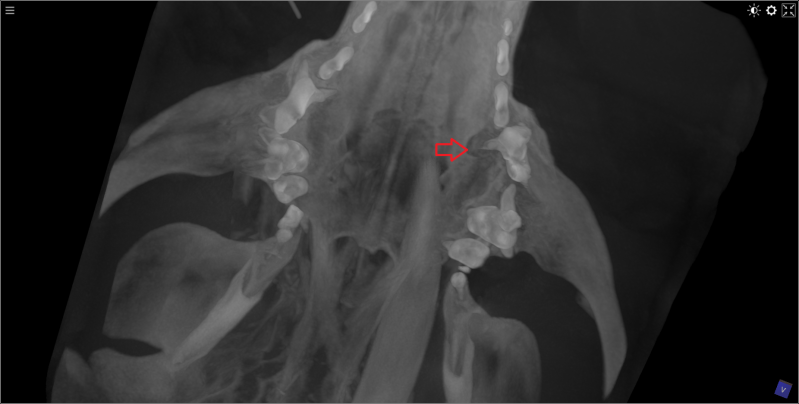

3D beeld van kop van kat met 9 breuken